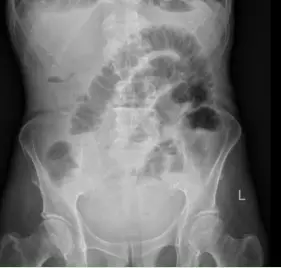

王大爷因腹痛、腹胀一周,伴呕吐、停止排气排便四天,被紧急送入我院肿瘤外科二病区。经影像学检查,王大爷被明确诊断为低位小肠梗阻。这意味着梗阻发生在小肠末端,肠道内容物完全无法下行,大量消化液和气体在肠腔内积聚,肠壁被持续撑胀,随时可能缺血坏死、穿孔,引发致命性腹腔感染。

导管开始工作后,积聚的肠内容物被持续引出,腹胀腹痛的症状一天天缓解。老人的肠道功能慢慢恢复,复查腹平片显示梗阻情况明显好转。在护理团队的精心照料下,老人从卧床不起到能下地活动,从禁食禁水到逐渐恢复饮食,一天天好起来。2月24日,王大爷顺利出院,重新回归了正常生活。